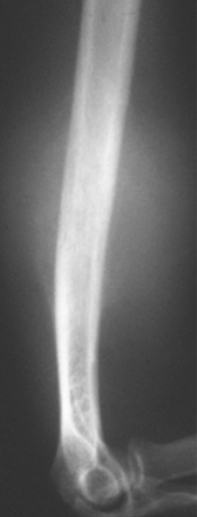

What is seen on imaging a GCT?

Xrays

Bone scan